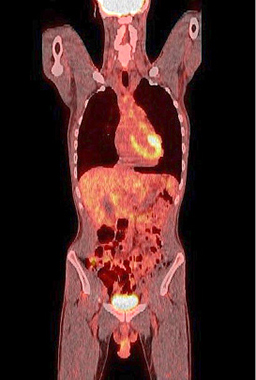

Figure 9. A normal finding of post-transplant PET/CT Scan

One year after the operation, a PET/ CT scan performed showed normal distribution of F-18 FDG and no signs of residual intraabdominal tumor (Figure 9). In the present period, the patient is disease free.